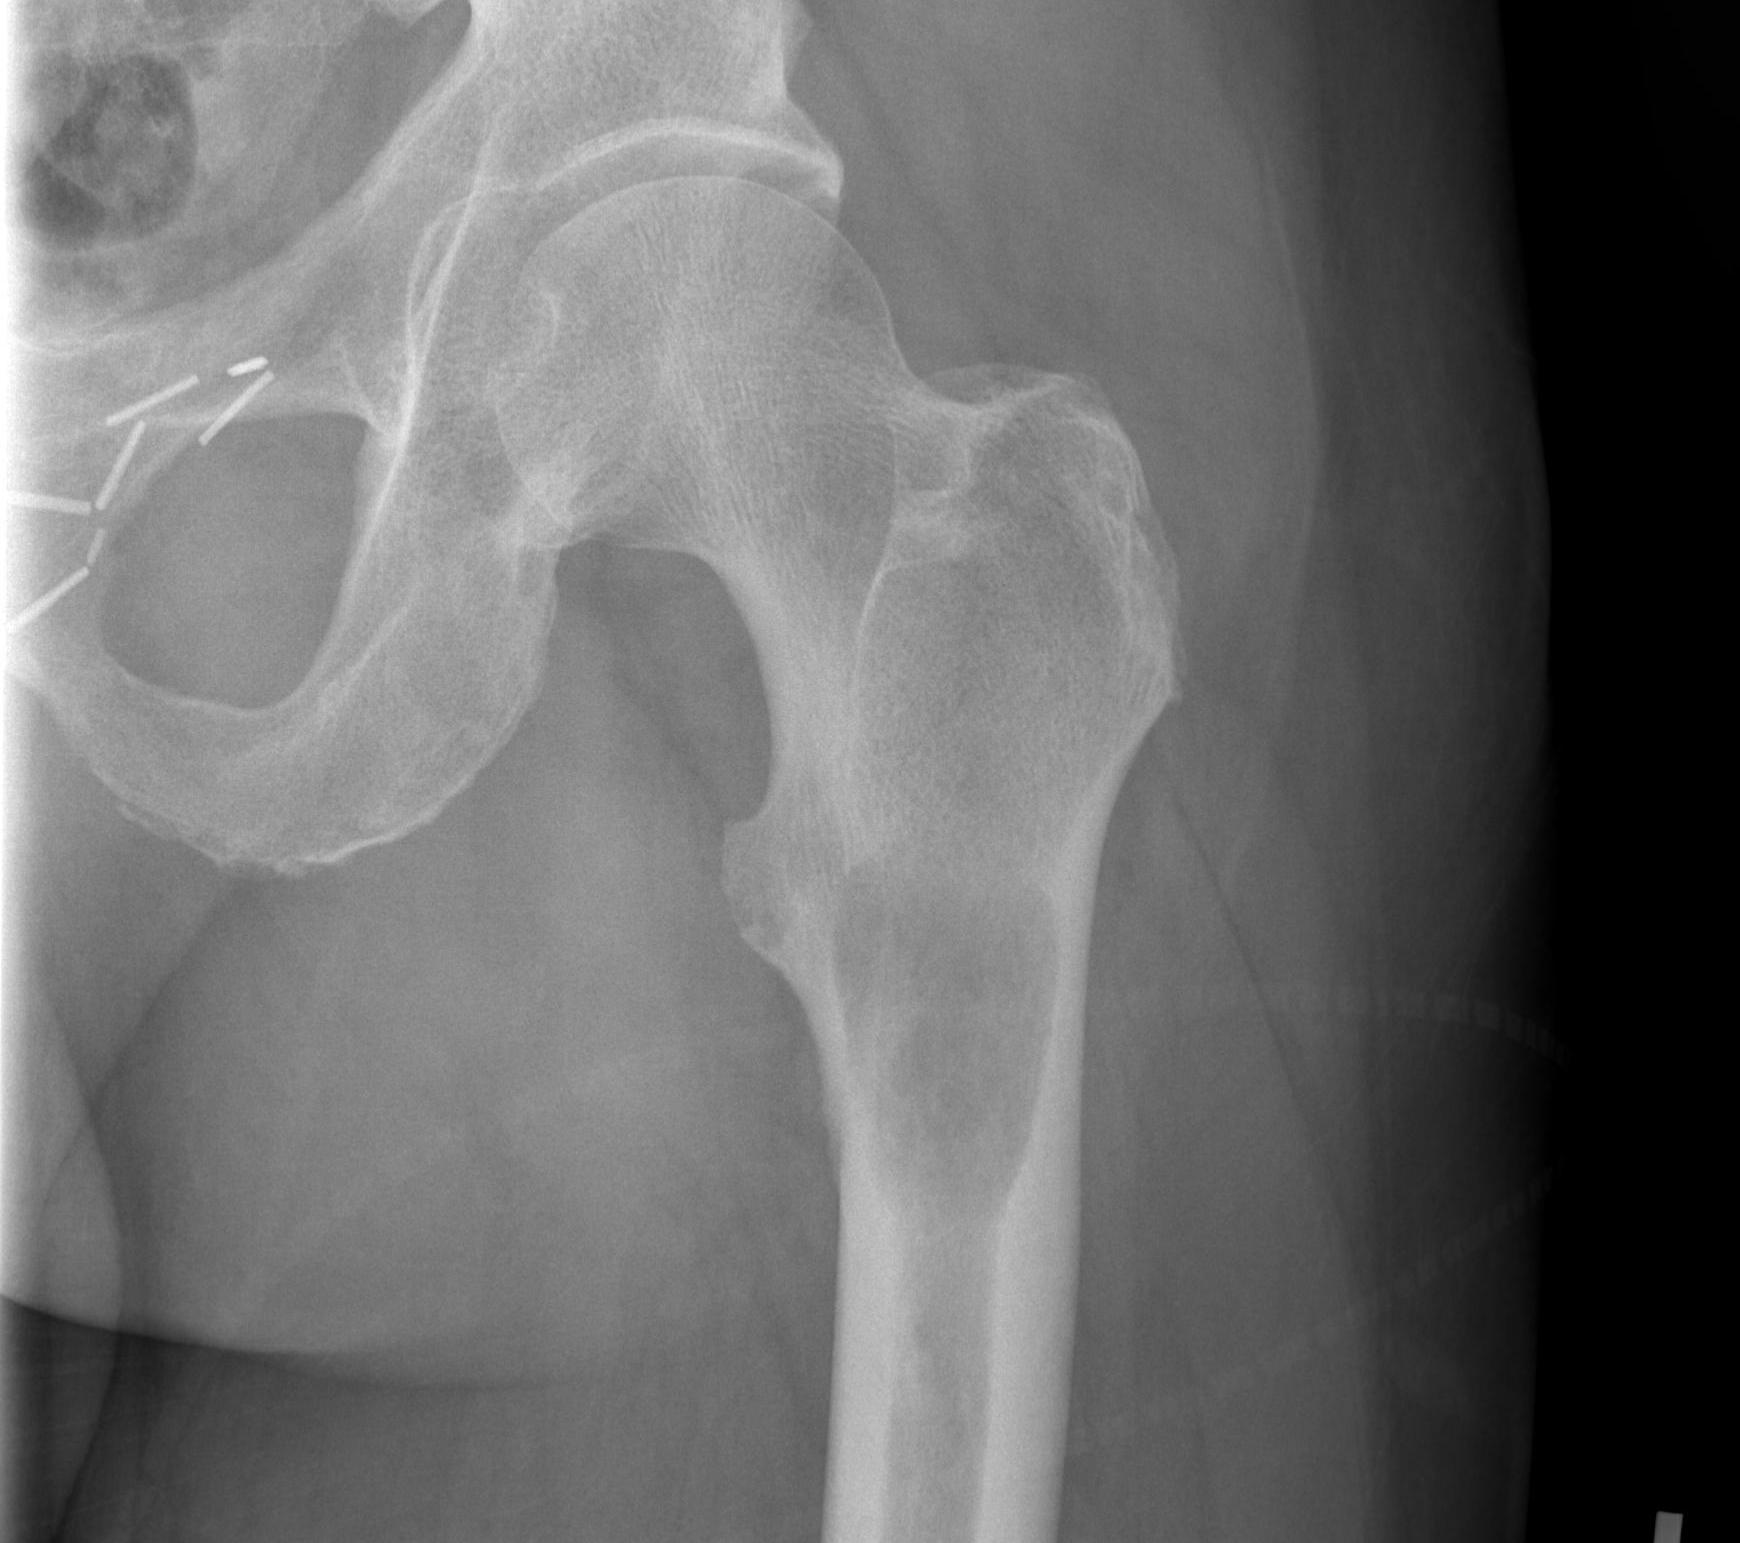

Subtrochanteric / Femoral shaft metastasis

Management

Reconstruction nail

- consider cement

- consider venting

- 217 patients treated with cephalomedullary nails for proximal femoral metastasis

- revision surgery required in 10%

- more common with survival > 7 months